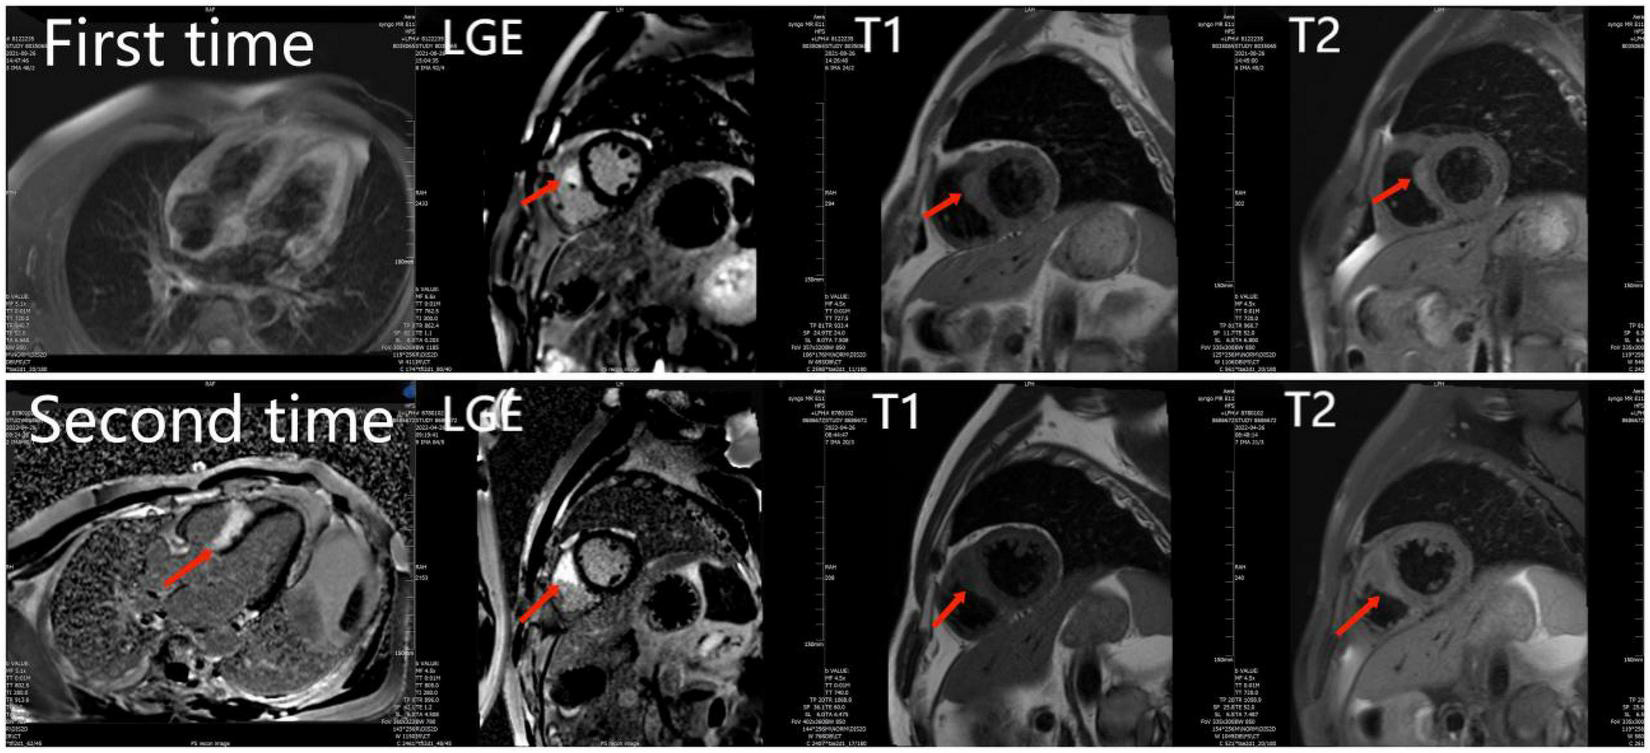

FIGURE 1

The first and second cardiac magnetic resonance show abnormal signals and LGE in the right ventricular surface of the ventricular septum. And the second time LGE was more severe than the first time.

Surgery and medication did not improve the patient’s symptoms within the following 7 months. In local hospital repeat CMR imaging showed that LGE was aggravated (Figure 1). Fluorine-18 fluorodeoxyglucose positron emission tomography (FDG-PET) demonstrated intense multifocal cardiac uptake in the interventricular septum and right ventricle without abnormal lesions in other parts of the body (Figure 2). Adenosine technetium-99m (99mTc)-sestamibi myocardial perfusion imaging showed that blood perfusion was decreased in the middle and basal segments of the ventricular septum. The doctor considered that arrhythmia might be caused by cardiac tumor, and suggested that the patient should undergo cardiac biopsy in our hospital.